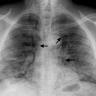

The authors report a case of a COVID-19 pneumonia patient with spontaneous pneumomediastinum and pneumopericardium in the absence of the use of invasive mechanical ventilation.